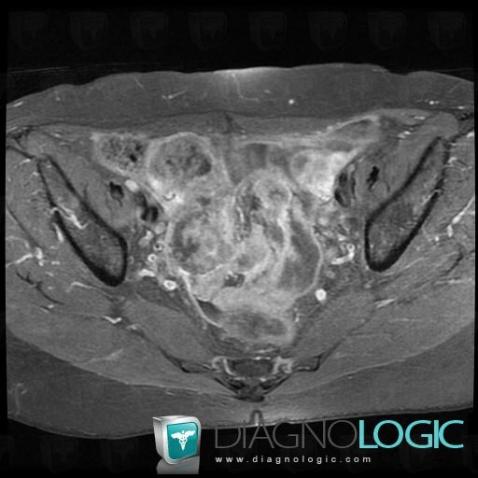

Serous cysteadenocarcinoma, Adnexa / Ovary fallopian tube, Pelvis / Perineum, MRI

Here is the specific information in the key image above:

- Diagnosis Serous cysteadenocarcinoma (link to Serous ovarian tumor), Location(s) Pelvis / Perineum, with gamuts Large pelvic mass, Cystic pelvic massAdnexa / Ovary fallopian tube, with gamuts Cystic adnexal mass